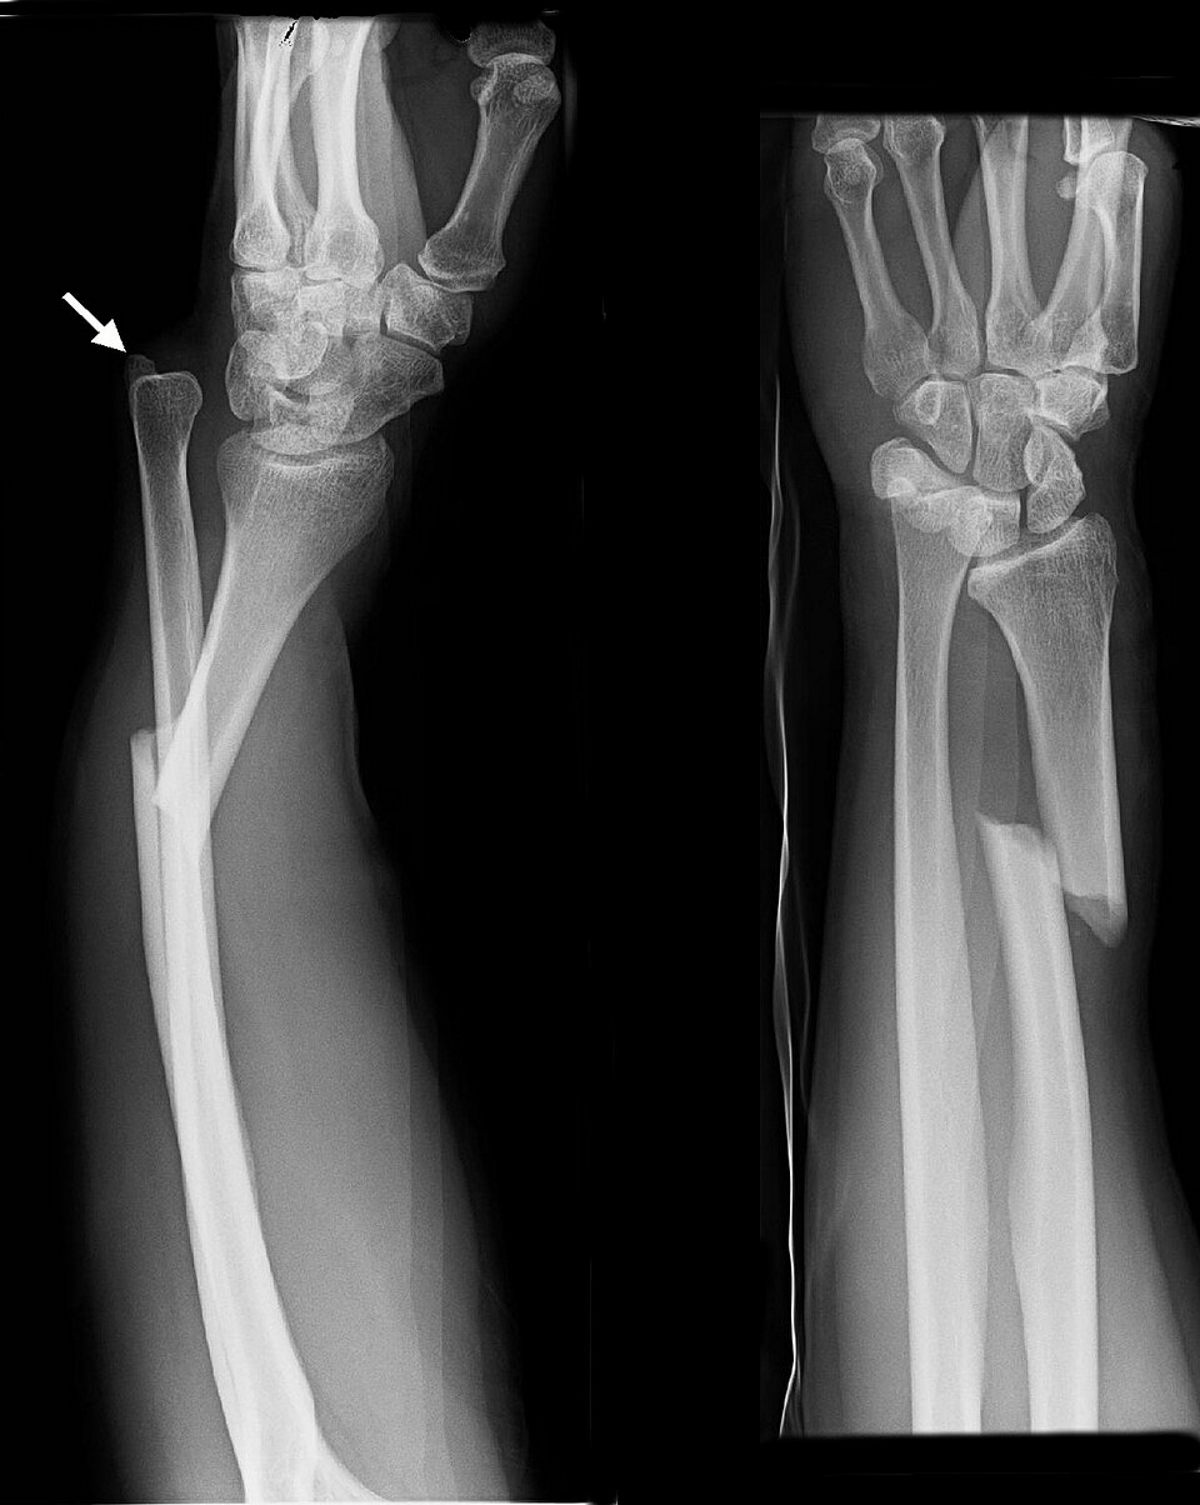

Describe what occurs in a galeazzi fracture

Fracture of distal radius + disruption of distal radio-ulnar joint (DRUJ)

You examine an xray and find a fracture of the distal radius, what structure should you also examine for damage/pathology

Distal radio-ulnar joint (incase of galeazzi fracture)